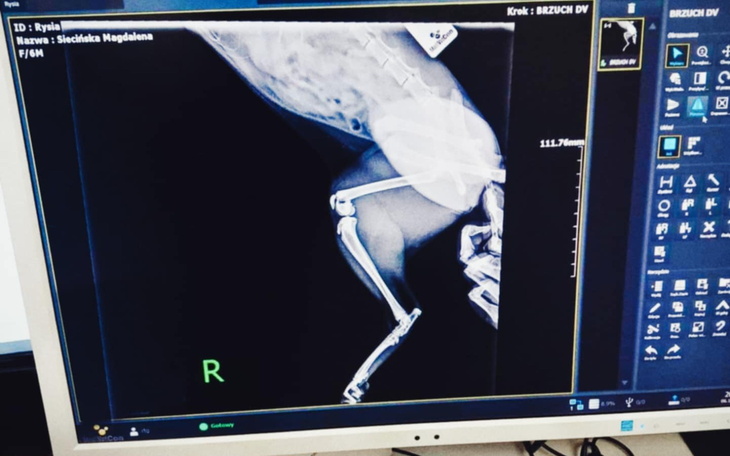

Potrzebuję waszej pomocy , rok temu przygarnęłam z ulicy kotkę ,Rysie zakochałam sie w niej od pierwszego wejrzenia i bardzo się do niej przywiązałam niestety jako kotka która żyła na dworze pewnego dnia uciekła między nogami przez otwarte drzwi gdy wchodziłam do mieszkania szukałam jej kilka godzin i znalazłam kiedy utykała i płakała szła za blokiem wystraszona nie wiadomo co sie jej stało , pojechałam z nią do weterynarza który po prześwietleniu stwierdził złamanie tylnych łap i uszkodzenie miednicy rysia jest mi naprawdę bardzo bliska lecz niee mam takich funduszy wiec proszę o wsparcie kazda chwila i każda złotówka się liczy